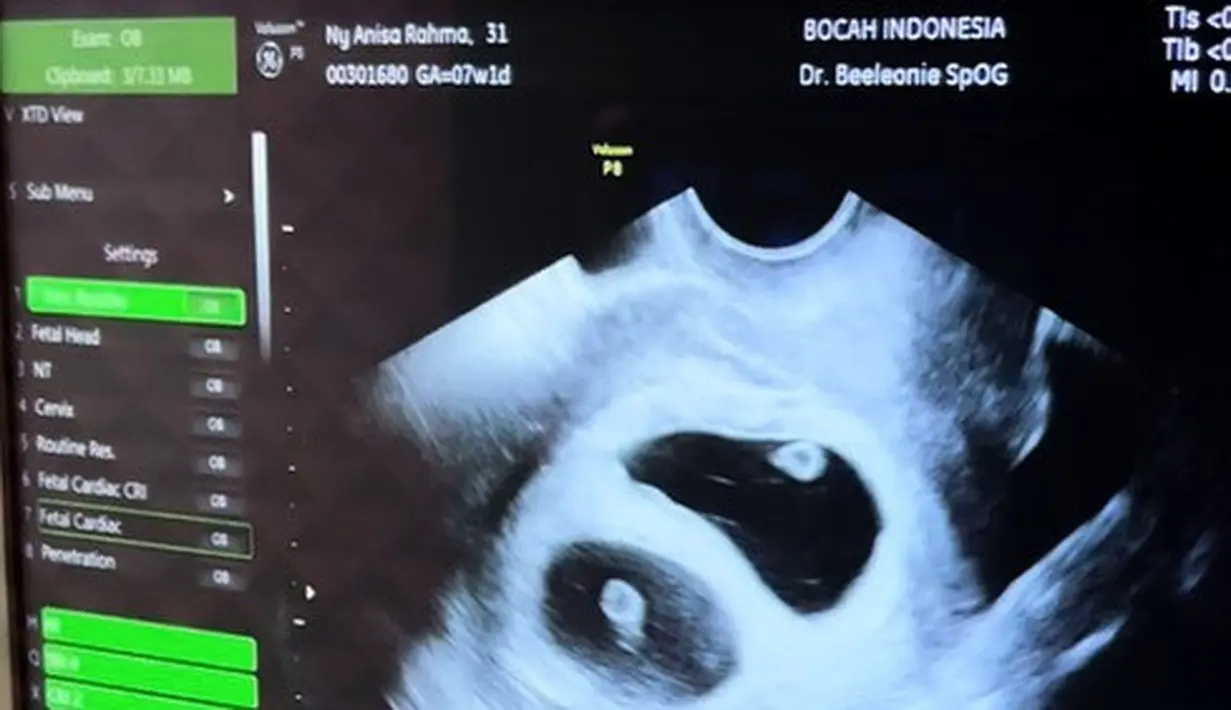

Tidak hanya bahagia atas kehamilannya, tapi juga karena ada bayi kembar dalam rahimnya. "Program bayi tabung yang aku jalani berjalan lancar dan berhasil..Dan yang buat kami terkejut juga, ada bayi kembar dalam rahim aku 😭 insyaAllah semoga Allah jaga selalu, kami berdua akan menyambut baby twins ini," lanjut Anisa Rahma yang juga memberikan semangat kepada pejuang dua garis. (Instagram/ananditodwis)